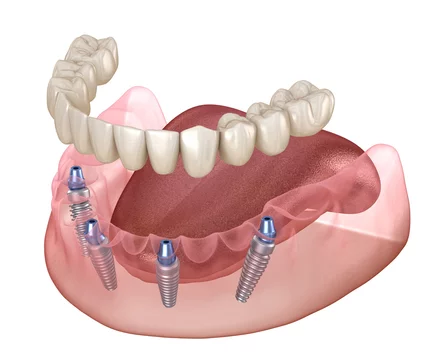

Read MoreProblems with Snap-In Dentures: What You Need to Know

Snap-in dentures, also known as implant-supported dentures, have become a modern alternative for individuals dealing with missing teeth. These removable dentures attach to dental implants in your jaw, offering more stability and security than traditional dentures. But while they provide convenience and improved functionality, they also come with their own set of complications and maintenance … Problems with Snap-In Dentures: What You Need to Know